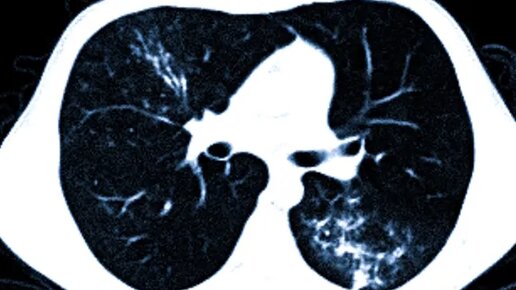

КТ при пневмонии и covid-19

Пневмония является серьезным инфекционно-вирусным заболеванием, которое поражает легкие. Вирусная пневмония является одним из типичных осложнений для коронавирусной инфекции 2019-nCoV (COVID-19). Поскольку некоторые виды вирусной пневмонии проходят бессимптомно, для выявления воспаления легких широко применяют визуализационные методы диагностики. Как правило, пневмонию замечают во время рентгена (нужно сделать боковую и прямую проекцию легких). Однако в некоторых случаях для подтверждения диагноза требуется прохождение компьютерной томографии легких...

Когда у пациента возникает соответствующая клиническая картина пневмонии (повышение температуры тела, кашель, боли в грудной клетке, одышка), выслушиваются хрипы при аускультации, врач обычно направляет его на рентген лёгких. Но начальной стадии, в первые дни развития пневмонии на рентгене лёгких может не быть характерных изменений. Диагностические возможности рентгена легких ограничены, так как при этом изображение получается в одной проекции. При прогрессировании воспаления лёгких и возникновении одышки, на рентгене, как правило, возникают соответствующие признаки пневмонии...